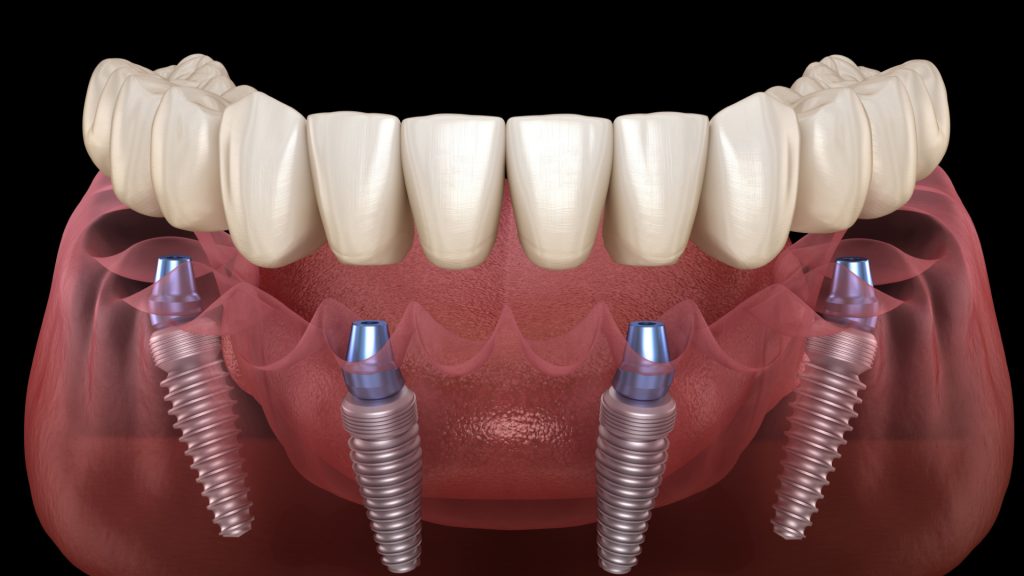

1. Endosteal Implants

The world ‘endosteal’ means ‘inside the bone’. This refers to its integration inside the jawbone, working as a natural root for prosthetic crowns. Endosteal implants are the preferred option for patients having enough jawbone to hold them in place.